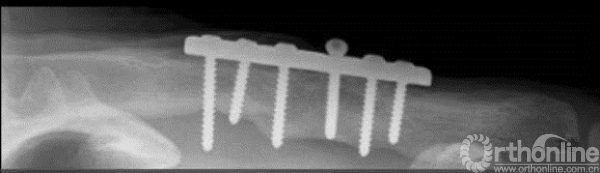

在临床应用中,当我们看到了这样的片子。那就要小心了!!

对于内侧的这个螺钉就很有可能造成损伤。根据文献回顾,造成损伤的螺钉,大约穿出的皮质>8mm。